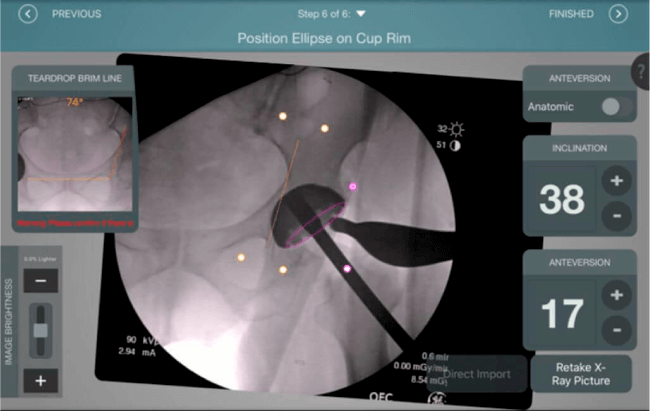

Inclinación y anteversión de la copa acetabular para una correcta colocación del implante.

Verificación de la posición deseada del implante que potencialmente puede ayudar a reducir la probabilidad de dislocación protésica y aumentar la estabilidad de la articulación.